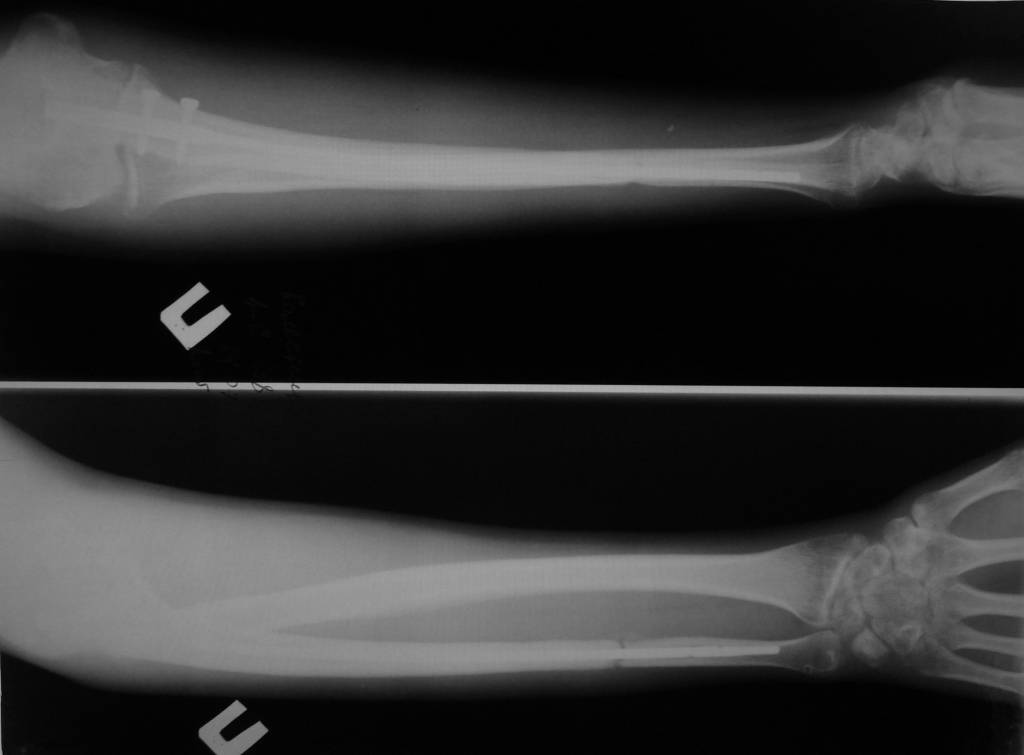

6 февраля 2011 года сломал локтевую кость со смещением. Поставили аппарат Илизарова. Вместо двух месяцев проносил четыре, срасталось медленно. Сняли, сказали разрабатывать и через 5 дней кость сместилась опять. 15 июня сделали вторую операцию, поставили дорогой стержень в кость, закрепили в области локтя на два шурупа. Перелом у меня в 1/3 ближе к кисти. Вторую часть кости одели на стержень, но не закрепляли. Также освежили концы костей, так как они зарубцевались и костномозговые каналы полностью закрылись.Месяц проносил лангету до плеча, потом сказали разрабатывать руку, но постепенно я начал чувствовать шевеление в месте перелома и щас чувствую.Щас опять хотят загипсовать уже всю руку на 2 месяца, но мне кажется что концы костей опять зарубцевались за 2 месяца зарастания "впустую" и даже в гипсе уже не срастется.По снимкам щель отчетливо видна. На руке вместе перелома нащупывается шишечка. Предположительно, что 1/3 кости, которая не прикручена к стержню, имеет хождение вдоль стержня.Кисти еще после аппарата Илизарова не поворачивается ладонью вверх и вниз. Имеет ход градусов 15 влево вправо и все.Что мне делать? Как еще восстановить руку? Еще одна операция? Исправит ли гипс на 2 месяца проблему? Мне 28 лет.

По этому снимку ничего плохого не видно. Нужна и вторая проекция. Когда сделан снимок?

Для того, чтобы предложить конкретный план выхода из этой ситуации, нужно более точное представление о проблеме - надо хотя бы увидеть свежие рентгенограммы всего предплечья в двух проекциях.